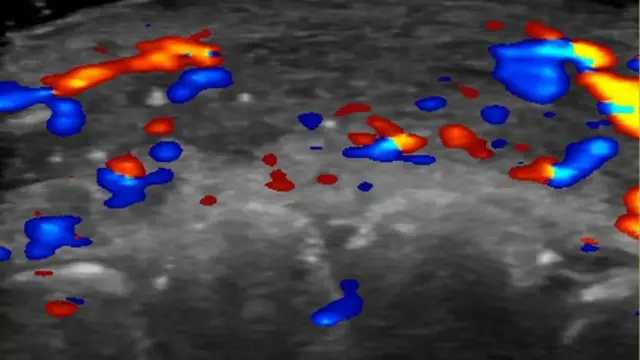

واستعان الباحثون بتقنية التصوير بالموجات فوق الصوتية بغية فحص مئة حالة من السيدات اللواتي أجرين عمليات حقن الفيلر والتي تسببت في حدوث نتائج غير مرغوب فيها.

وتُوصى العيادات حالياً باعتماد هذه التقنية التصويرية أثناء حقن الفيلر في الوجه، تفادياً لحدوث أي ضرر للشرايين المجاورة.

وأظهرت الأشعة بالموجات فوق الصوتية عدم تدفّق الدم في الأوعية الدموية الصغيرة التي تصل الشرايين السطحية بالعميقة في الوجه، لدى أقل من نصف الحالات التي شملتها الدراسة.

كما لوحظ، في نحو ثُلث الحالات، عدم تدفق الدم في الأوعية الدموية الكبيرة.

ولتفادي أي مضاعفات منذ البداية، يوصى حالياً باستخدام الفحوصات بالموجات فوق الصوتية لتخطيط مواقع الحقن بدقة في العيادات.

وفي حال حدوث مضاعفات، يُمكن للموجات فوق الصوتية أن توجّه الأطباء إلى المواقع التي تتطلب التعامل معها بالعلاج.

وتقول سيغريست: "في حال عدم اعتماد الموجات فوق الصوتية كدليل، تُجرى عملية الحقن على أساس الفحوصات السريرية فقط، وهو ما يعني إجراء عملية الحقن بطريقة عشوائية".

وتضيف: "لكن إذا كان باستطاعتنا رؤية ما تكشفه الموجات فوق الصوتية، فذلك يساعدنا في توجيه العلاج نحو الموقع الدقيق لحدوث الانسداد".

وتشير إلى أنه بدلاً من إغراق المنطقة بعقار "هيالورونيداز" لإزالة الفيلر، يمكن للممارسين إجراء حقن موجّهة تستعمل كمية أقل من المادة وتؤدي إلى نتائج علاجية محسّنة.

وتقول الجمعية البريطانية لجراحي التجميل إن الاعتماد على الموجات فوق الصوتية يتنامى، إلا أنه لم يتحول بعد إلى روتين أو معيار قياسي للعلاج.

وتعد الموجات فوق الصوتية تقنية غير غازية، كما أنها لا تعتمد على الإشعاع وتحويله إلى أيونات، ولم يُعرف لها أي آثار ضارة حتى الآن.

وتقول نورا نوجنت، رئيسة الجمعية البريطانية لجراحي التجميل، إن استخدام الموجات فوق الصوتية يُظهر فائدة كبيرة في شتى مجالات الجراحة وعمليات التجميل.

ويسهم تحديد مواقع الأوعية الدموية بدقة في توفير معلومات مهمة تمهيداً لتقديم العلاج.